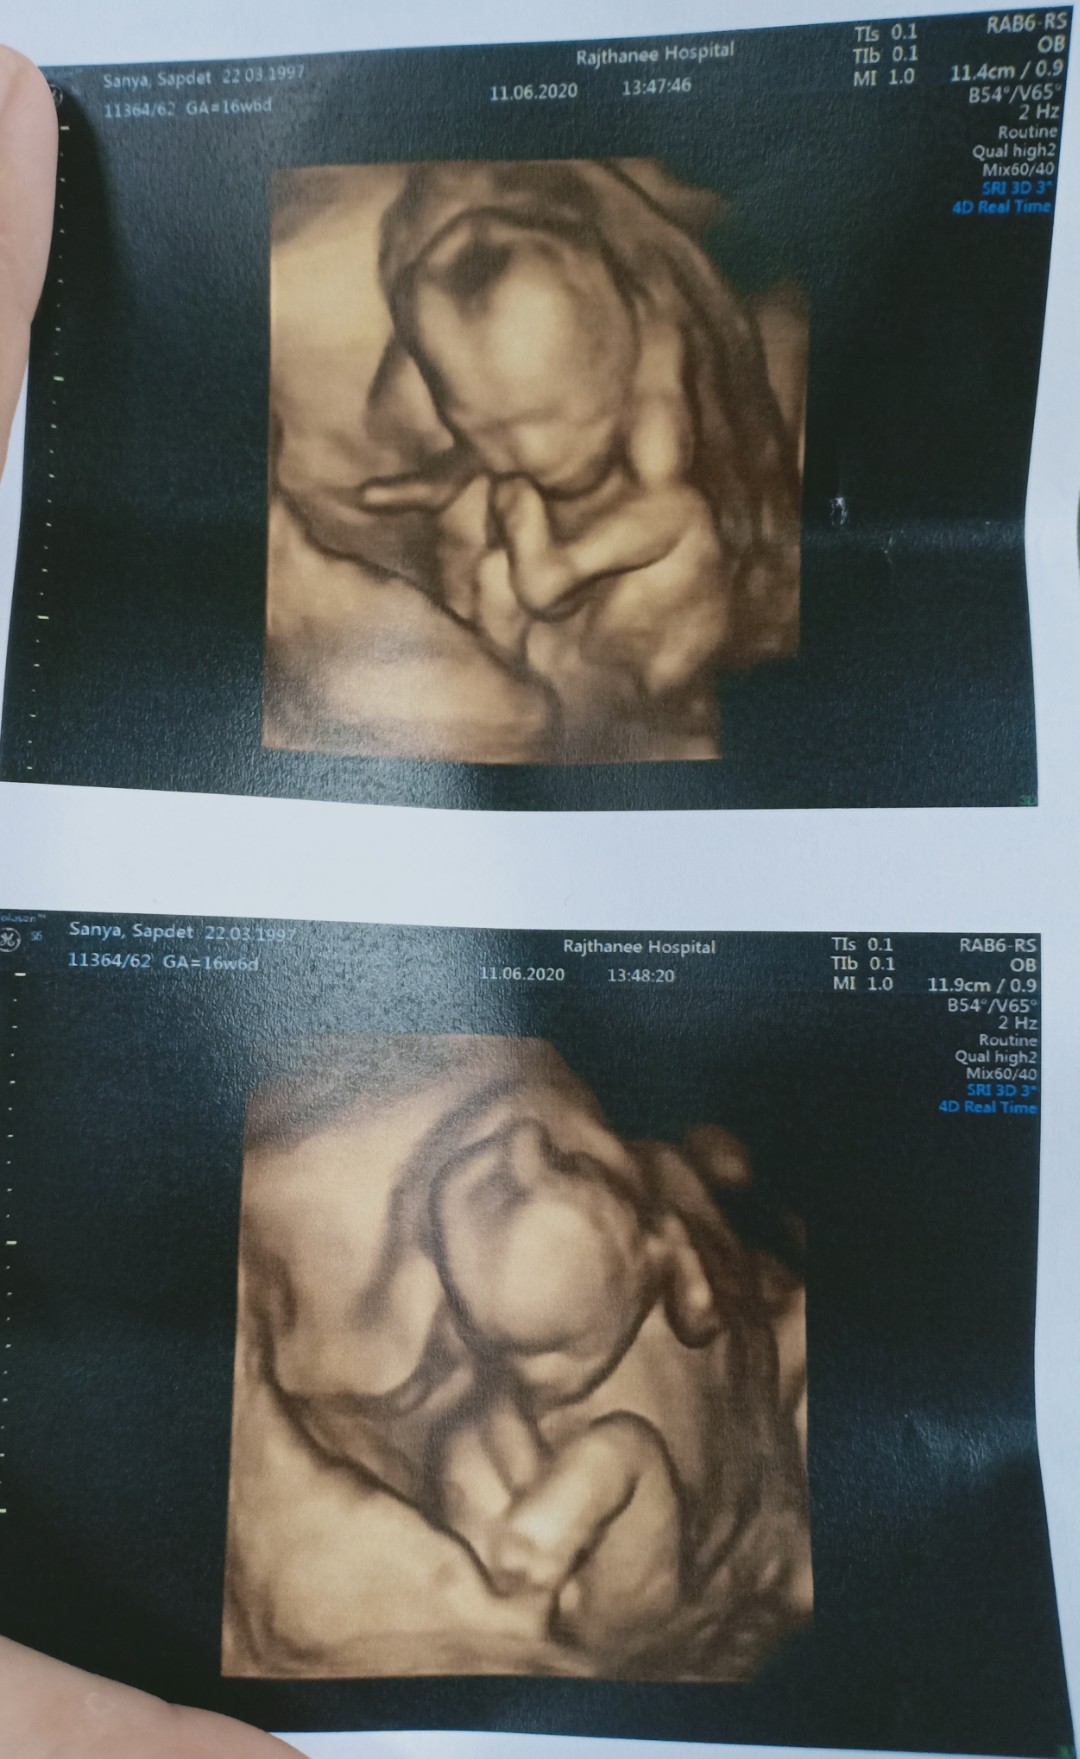

อันนี้ซาว4มิติใช่มั้ยค่ะ

17w จ้า กำหนดคลอด 21/11/63 ค่ะ